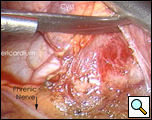

In the operating room, under general anesthesia and one lung ventilation, the thoracoscope was introduced at the right midaxillary line and the 7th intercostal space (Video 1 below). The cyst was readily visualized at the anterolateral aspect of the right pericardium, measuring approximately 9x6cm (Figure 3). The phrenic nerve was seen posterior to the cyst. The second incision was made at the anterior axillary line in the 4th intercostal space. A ring clamp was used to grasp the cyst (Figure 4). The third incision was made at the scapula line in the 5th intercostal space. Thoracoscopic scissors and cautery (at a low setting to minimize the chance of cardiac arrhythmias) were used through that port to dissect the cyst from the pericardium (Figure 5). The connection between the cyst and the pericardial space was identified. It was small, and was divided with the scissors. The dissection of the posterior aspect of the cyst completed the removal. The phrenic nerve was clearly visualized at all times. The pathology report confirmed the diagnosis of a benign mesothelial-lined cyst (Figure 6).

| Figure 3.: Intraoperative view of pericardial cyst. | Figure 4. Ring clamp retraction of pericardial cyst. |

| Figure 5. Resection of cyst with view of phrenic nerve. | Figure 6. Resected specimen |